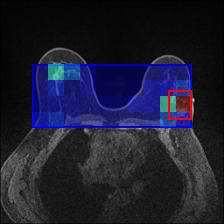

Based on , we select the pixels with activations higher than the top th percentile () and produce a binary interpretability map denoted as where . In this work, we use . Then, we estimate the tightest bounding box around where . Given the bounding box estimation for the interpretability map and the ground truth , we calculate . Visual summary of both the pointing game and the IoU overlap are provided in Figure 2.

Using the trained models with state-of-the-art performance, we follow the protocol detailed in Section 2.4 and present experimental results on interpretability in Figure 3, Figure 4, and Table 3. In particular, Figure 3 illustrates several qualitative examples, while Table 3 displays pointing game accuracy and mean IoU scores. Finally, Figure 4 represents IoU distributions represented in the form of boxplots. Based on these results, we make the observations below.

Qualitative results can be misleading. In Figure 3, we present qualitative interpretability outputs for all methods considered. As can be seen, depending on the selected subset of images and the method, both accurate and inaccurate interpretability maps can be found. These findings emphasize the danger of making strong claims about interpretability methods based solely on qualitative results, including attention maps.